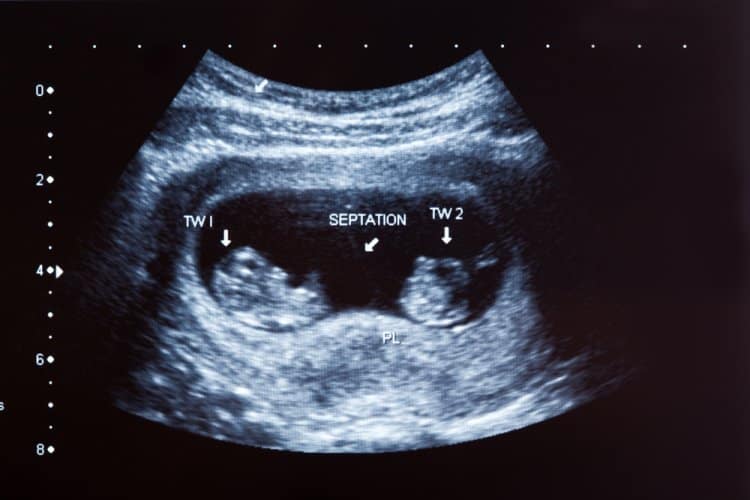

Çocuk sahibi olmak isteyen kadınların birçoğunda ikiz gebelik görülebilmektedir. Her gebelikte bitkinlik ve halsizlik olabilmektedir. Hem normal hamilelikte hem de ikiz bebeğin hamileliğindeki belirtiler aşağı yukarı benzerlik gösterir. İki ceninin kalp atışı duyulur bebeğinizin ilk ultrason muayenesinde doktorunuz iki ayrı kalp atışı duyduğunu söyler. Annelik sütyenleri giymek ağrıyı azaltmaya yardımcı olabilir. Bu daha genel ifadeyle ikiz bebek anlamına gelmektedir.